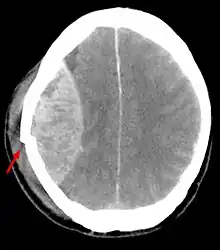

![]() TAC mostrando contusiones cerebrales, hemorragia intracraneal entre los hemisferios, hematoma subdural y fracturas craneales[1] | ||